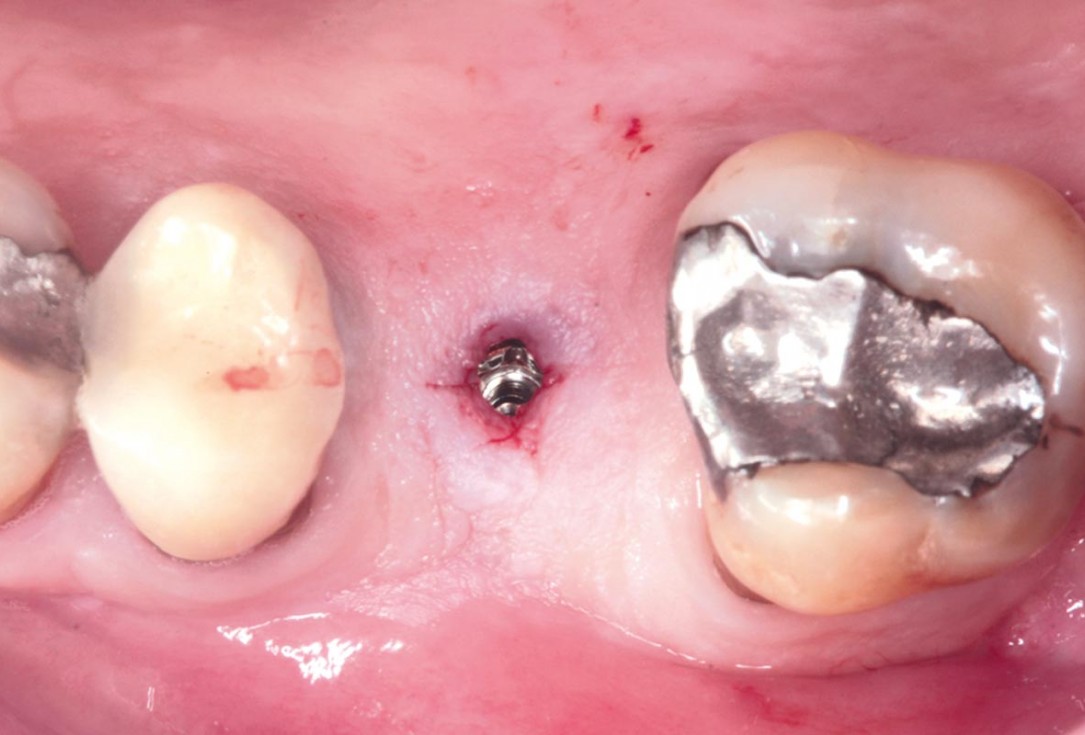

28/35 - Application of the healing cap after the second stageMaxillary sinus cyst removal using the Crocodile Technique and subsequent lateral sinus lift - Dres. C. Scognamiglio and A. Perucchi